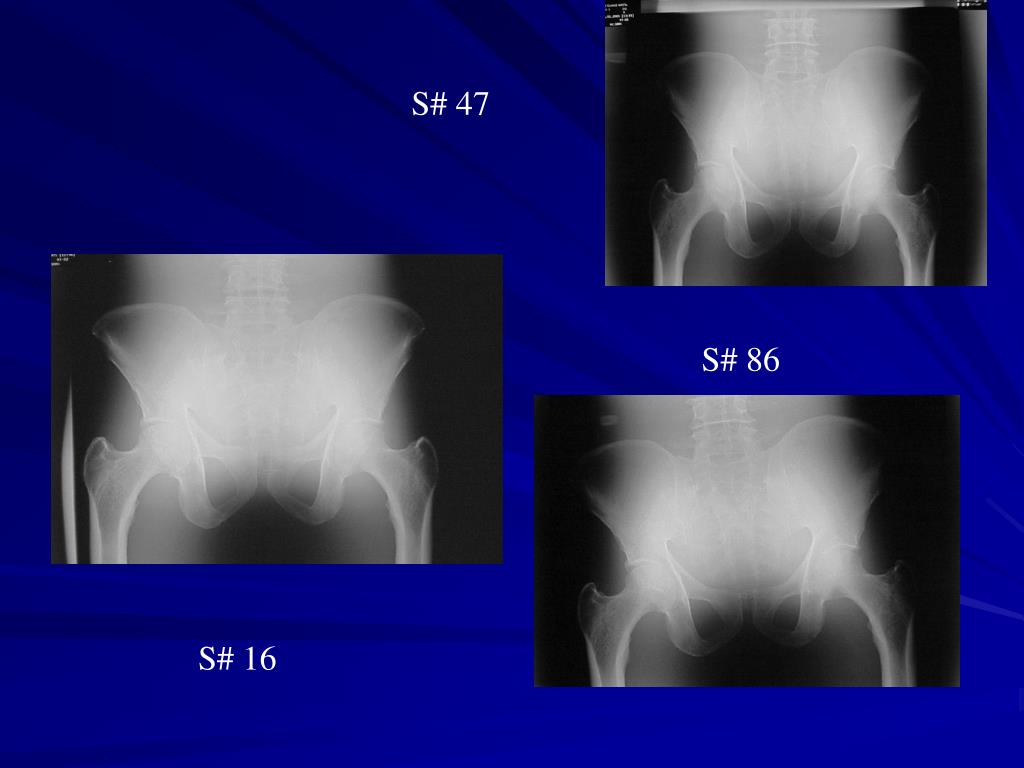

25. S# 47 S# 86 S# 16